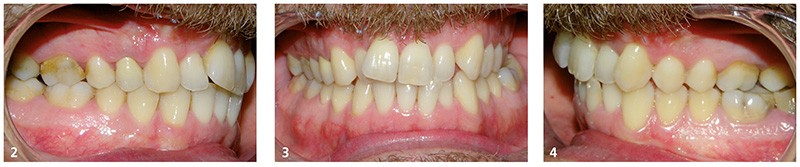

Il présente une malocclusion de classe II subdivison gauche totale par mésioposition du secteur 2 avec une déviation dentaire du milieu maxillaire à droite (fig. 2 à 6) dans un visage équilibré (fig. 7 et 8).

La mésioposition du secteur 2 a entraîné un encombrement antérieur avec malpositions des incisives supérieures, la 12 étant en occlusion traumatogène, en bout à bout avec son antagoniste (fig. 3). Dans le sens transversal, il existe une endoalvéolie maxillaire avec occlusion inversée postérieure à gauche. À l’arcade mandibulaire, l’encombrement est modéré (fig. 6).